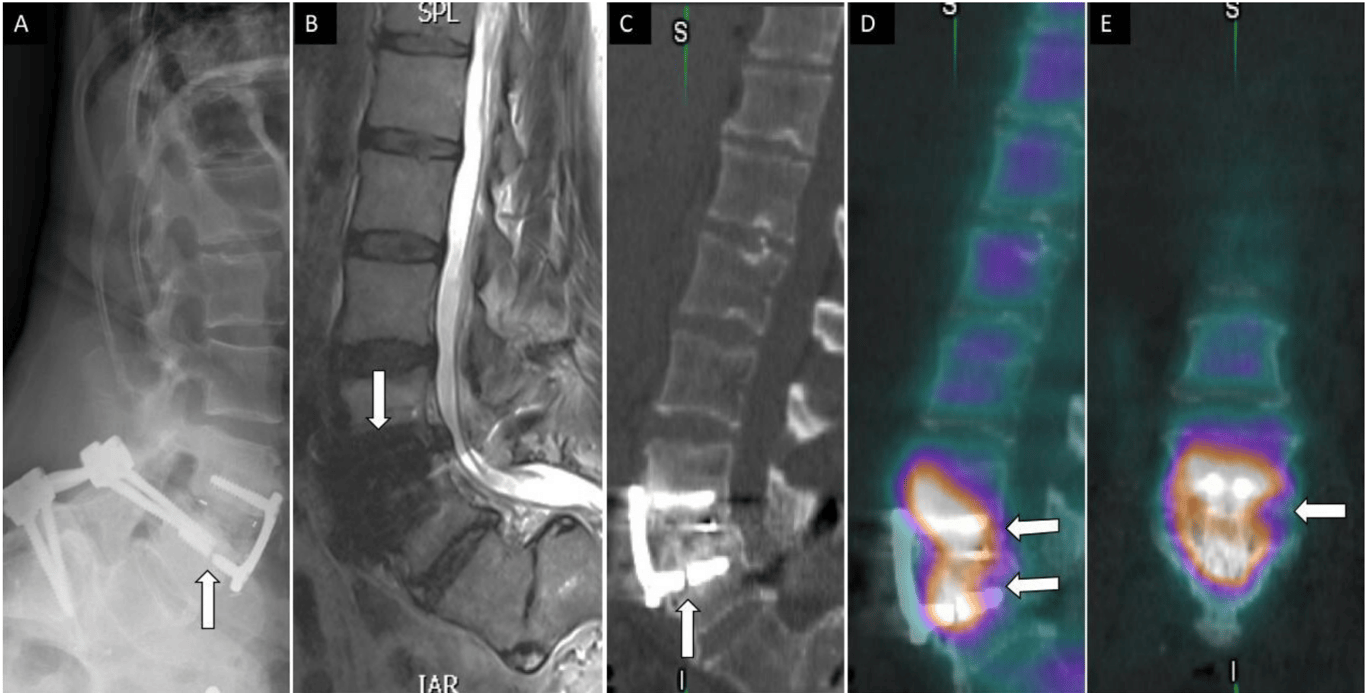

A 56-year-old woman presented with low back pain after prior L4 to S1 posterior instrumented fusion and subsequent standalone L3 to L4 anterior lumbar interbody fusion with anterior plate fixation. Lateral lumbar spine radiograph (A) shows fractured screw related to anterior instrumentation at the level of L4 (arrow). Sagittal T2 magnetic resonance imaging (B) shows no evidence of acute central canal stenosis and metal artifact (arrow) related to instrumentation. Sagittal noncontrast computed tomography (C) demonstrates fractured screw into the L4 vertebral body and sclerotic changes within the bone. Fused sagittal and coronal images demonstrate increased osteoblastic activity and radiotracer uptake within the L3 to L4 disc space concerning for hardware loosening and pseudoarthrosis